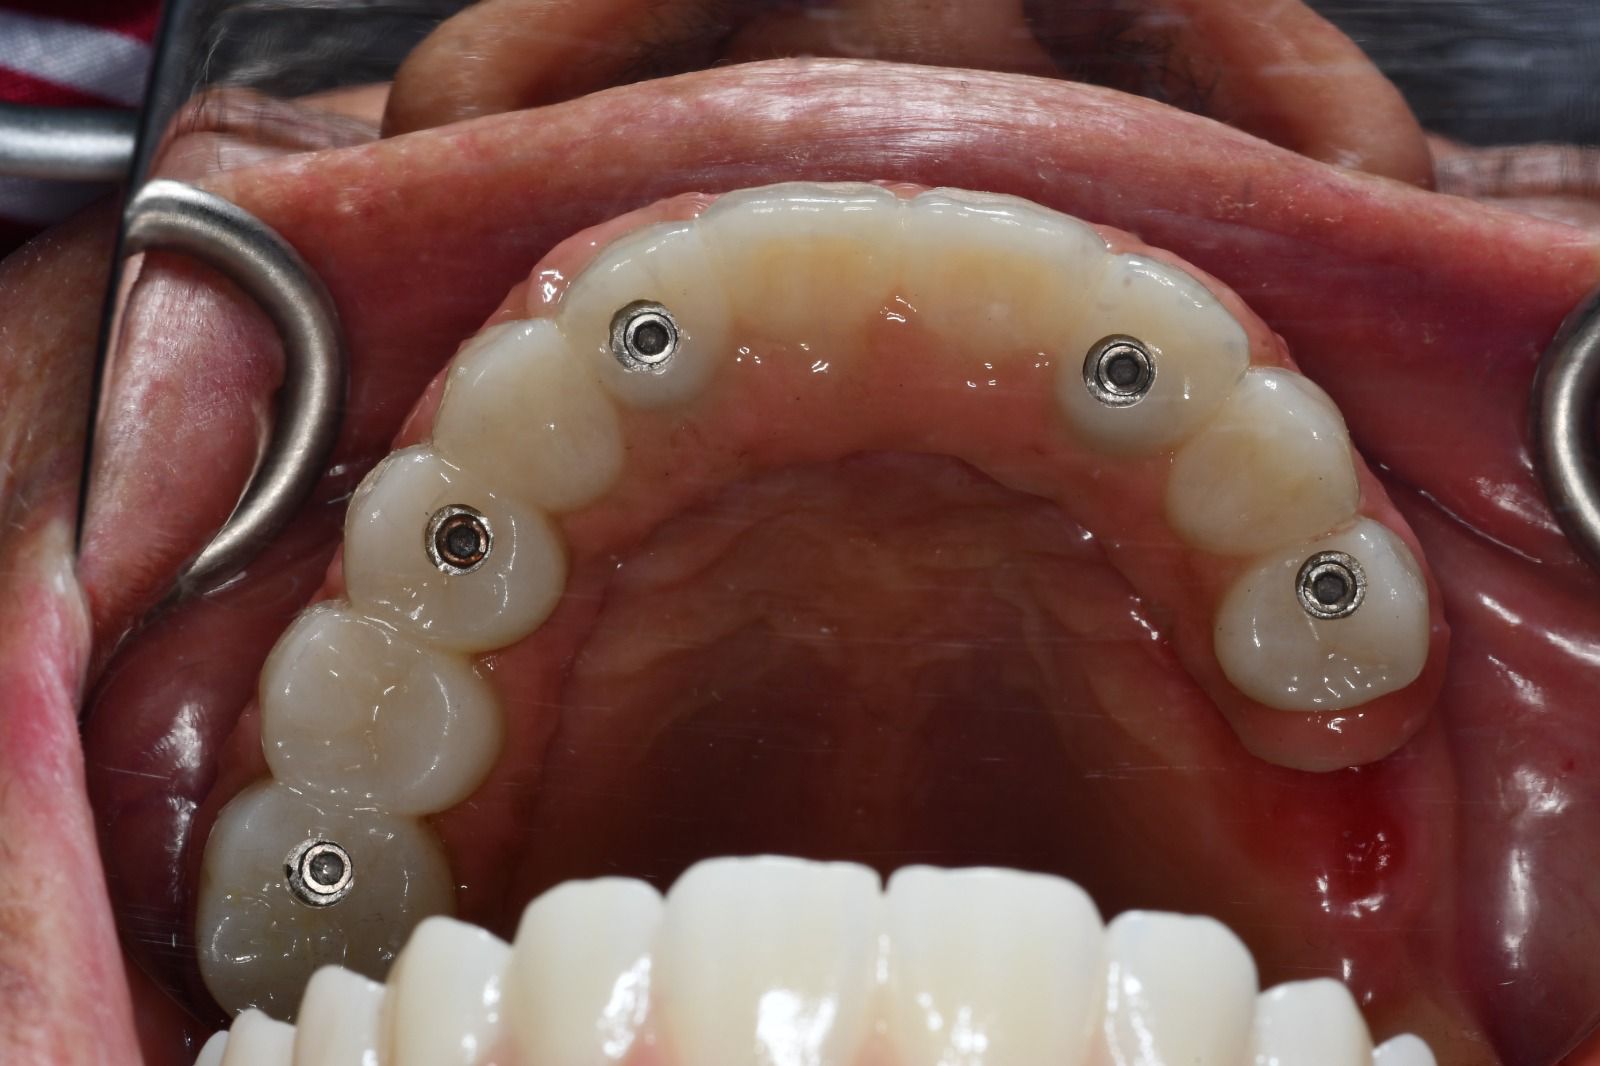

Casos de éxito

Estos son algunos de nuestros casos de éxito, mostrando el antes y después de nuestras intervenciones.

Rehabilitación de la arcada superior con zirconia monolítico multicapa.